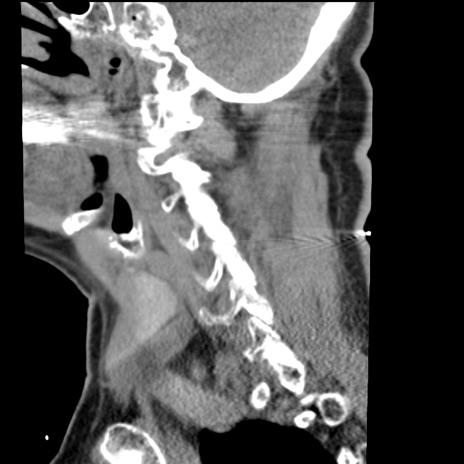

症例50 頚椎CT(矢状断像)

【症例】60歳代女性

【主訴】後頭部〜右後頸部にかけての痛み

【現病歴】本日飲食店でコーヒーを飲んでいたところ、突然後頭部〜右後頸部にかけて痛みが出現し、右上肢の感覚障害を伴ったため救急要請。

【身体所見】脳神経学的に明らかな異常所見を認めず。右上肢に軽度の感覚障害あり。

異常所見と診断は?

頚椎CT